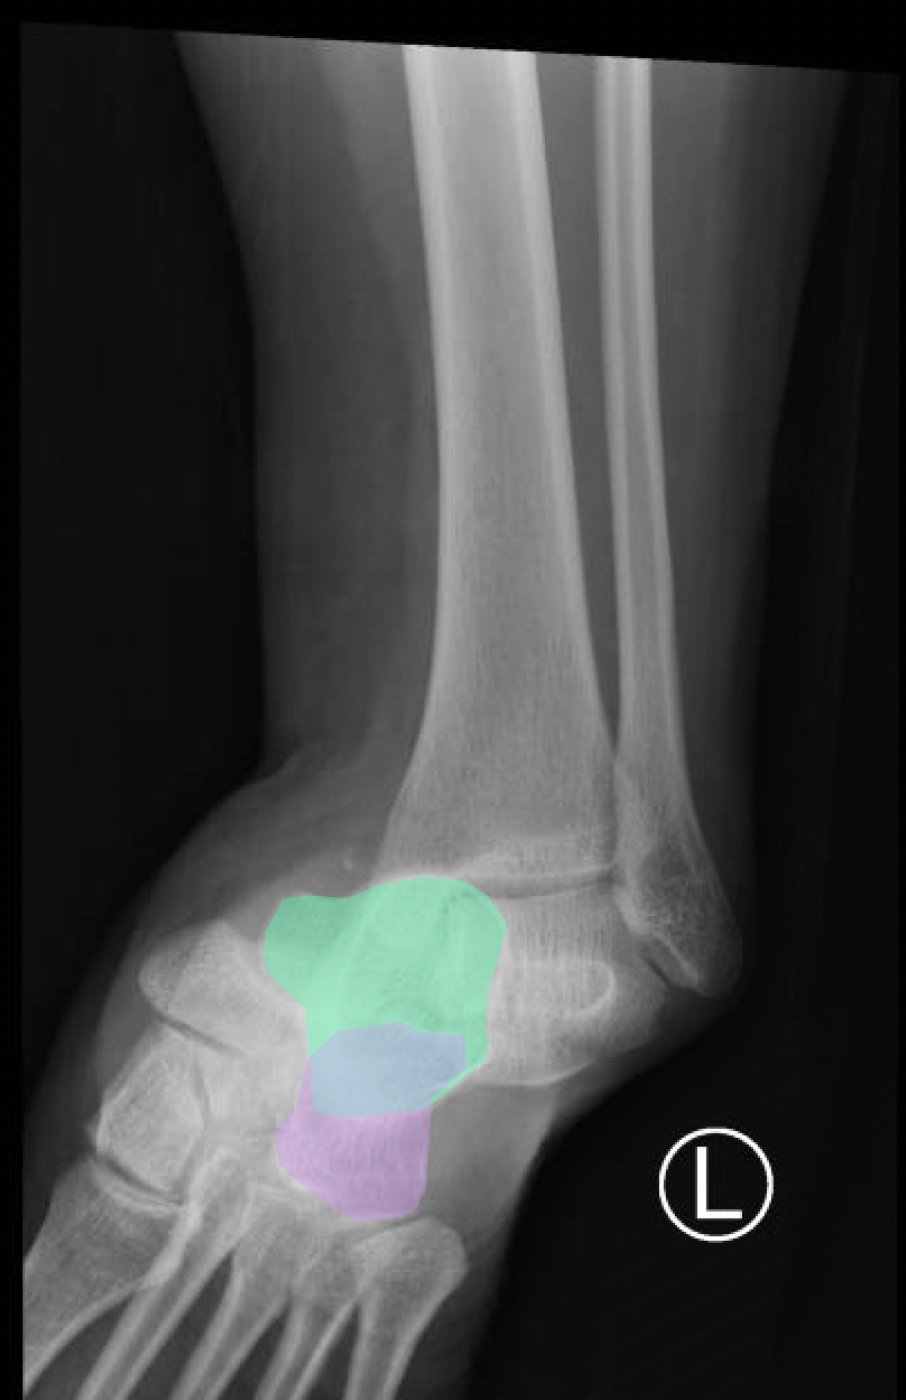

The X-rays were significant for a subtalar dislocation. The calcaneus (red) is laterally displaced with respect to the talar head (orange), and the white lines indicate the normal articular surface. Additionally, there was a talonavicular dislocation, as seen in the fourth image: the talus (green) and navicular bone (purple) overlapping suggests a dislocation. In a normally aligned foot, the boundaries of the two bones create a point of articulation.